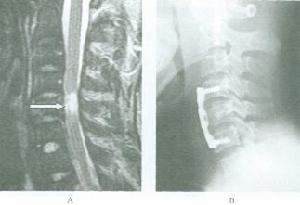

短頸畸形1.單純中下位頸椎融合引起的短頸畸形,早期常無神經症狀,不需特殊處理,但應注意避免頸椎過度活動,防止外傷,延緩頸椎退變的進程;對頸部外觀醜陋者,可行雙側頸部皮膚“Z”型成形術或雙側胸鎖乳突肌切斷術改善外觀。晚期因頸椎退變引起椎管狹窄出現脊髓受壓症狀者,可根據脊髓受壓部位行前路或後路減壓術。

3.短頸畸形創傷合引起脊髓損傷但不伴有骨性損傷者,應先採用非手術治療,如顱骨牽引或枕頜帶牽引,症狀消失後給予頭頸胸石膏固定;伴明顯骨折脫位者,則先採用顱骨牽引使之復位,然後根據神經症狀變化情況選擇治療方案。